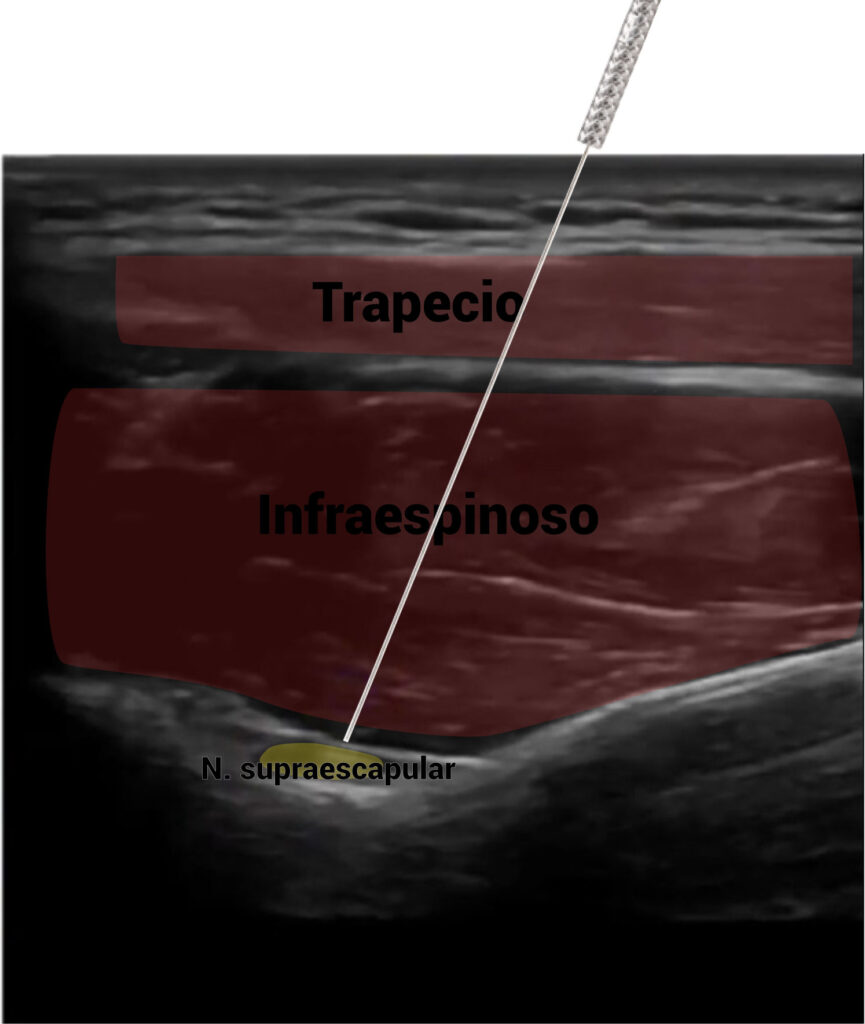

Abordaje invasivo del nervio supraescapular

El abordaje que recomendamos para el nervio supraescapular es en la fosa supraespinosa. Mediante nuestra guía ecográfica, detectaremos una pequeña depresión, correspondiente a la escotadura de la escápula. Es ahí donde se encontrará el nervio supraescapular.

La entrada se hará en eje largo, atravesando con nuestra aguja los vientres musculares del trapecio, supraespinoso, hasta llegar al nervio.

Cuando hagamos la estimulación eléctrica, el paciente tendrá una reacción de rotación externa del húmero y ligera abducción. Esto es por la estimulación motora de este nervio a los músculos supraespinoso e infraespinoso.